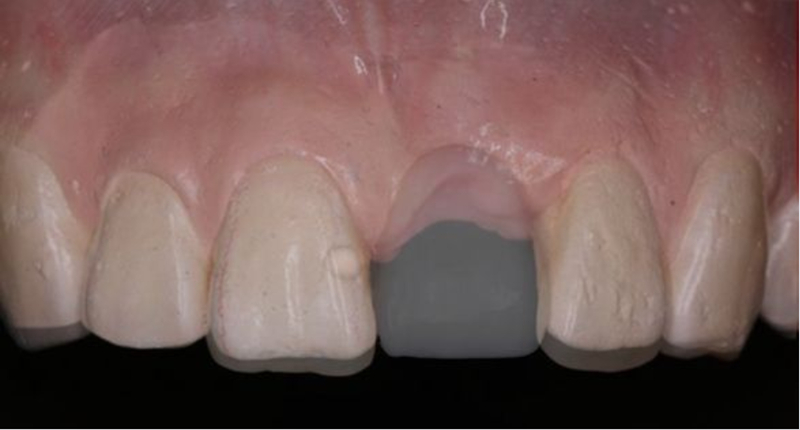

術(shù)前制取參考模型,排美學蠟型,實現(xiàn)以美學修復(fù)為導(dǎo)向的種植

使用U型管作為局部托盤,在石膏模型上,應(yīng)用聚醚硅橡膠進行印模

待硅橡膠凝固后,在印模中21缺牙區(qū)灌注阻射性材料(磷酸鋅或硫酸鋇/自凝牙托粉)

待阻射性材料凝固后,修整其邊緣及組織面

戴入患者口內(nèi),檢查U型管就位與石膏模型就位一致

檢查U型管及印模在口內(nèi)就位與石膏模型上一致

患者佩戴此U型管開合拍攝CBCT,其中可以獲得缺牙區(qū)修復(fù)體的切端及齦緣等信息

患者佩戴此U型管開合拍攝CBCT,U型管中的放射標記點清晰顯影